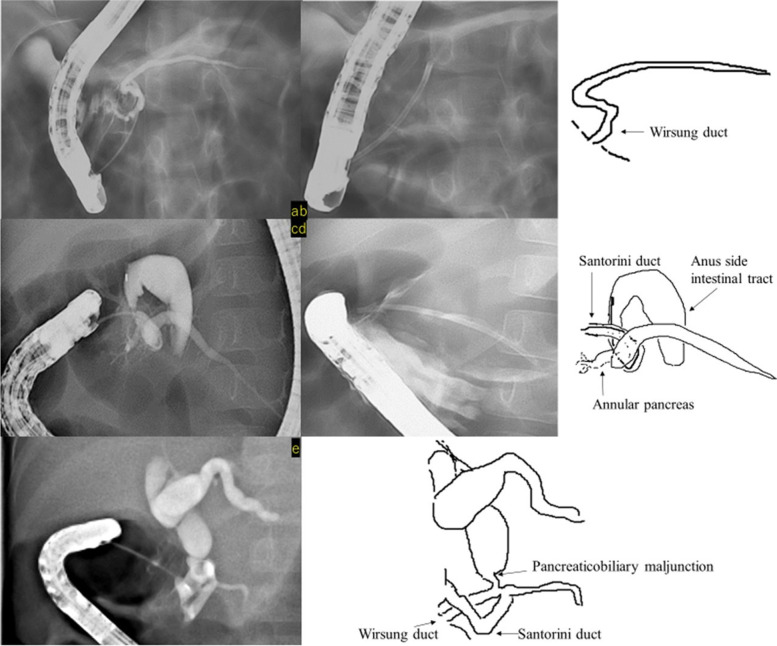

All three patients with chronic pancreatitis had diffuse dilatation and wide irregularities involving the pancreatic duct, and pancreatic duct stents were emplaced. EPS was performed repeatedly; however, all patients eventually underwent pancreatic stent removal and were followed up without recurrence of pancreatitis (Fig. 5).

In Case 5, ERCP was performed 6 times, and the stenosis of the pancreatic duct was alleviated by placing a stent. No recurrence of pancreatitis has been observed for 14 years and 5 months after stent removal (Fig. 5a, b and c).

Pancreatic divisum and Others

Of two patients with pancreas divisum, it was difficult to insert a stent into the accessory papilla in Case 8 and only contrast imaging was performed; the patient is currently being followed-up on an outpatient basis. In Case 9, a pancreatic duct stent was placed from the accessory papilla to the caudal pancreatic duct, and the patient was confirmed to have no symptoms of pancreatitis, after which endocscopic minor papilla shincterotomy was performed. Fifteen months have passed since the endocscopic minor papilla shincterotomy was performed; however, no recurrence of symptoms has been observed (Fig. 5d, e and f).